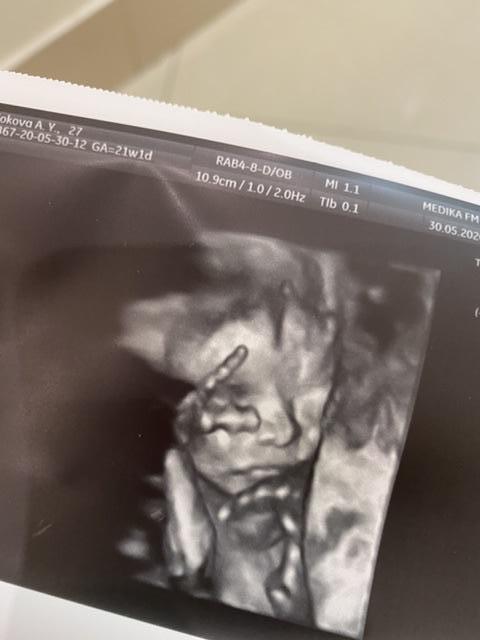

4D УЗИ в 21,1 неделю [ФОТО]

Всё-таки сходила ещё раз на второй скрининг - на этот раз платно и в 4D. Малышка благополучно проспала весь приём и игнорировала попытки врача её расшевелить 🙂

Зато такие милые фотографии получились, не то что в прошлый раз. Насмотреться не могу! Всего 21 неделька, а уже такой полноценный красивый человечек!

Класс!!!! И носик и губки как у взрослого человечка уже

Прижалась так сладенько к маме и спит